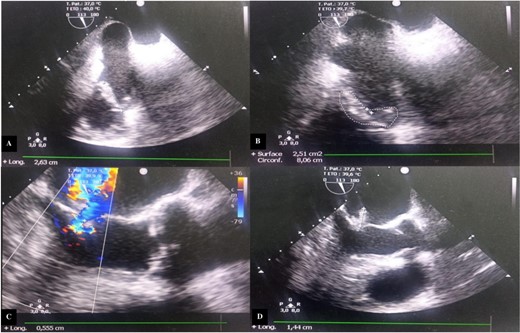

Transesophageal echocardiography (TEE) showed a mitral valve with vegetation prolapsing into the left atrium and a tricuspid valve with vegetation measuring 26 mm in its largest dimension, prolapsing into the right atrium (Fig. 2).

Transesophageal echocardiography images. (A) Incidence 113° showing vegetation attached to the free edge of the anterior tricuspid leaflet measuring 26.3 mm in long axis. (B) Surface area of the vegetation attached to the anterior tricuspid leaflet estimated at 2.51 cm2 and circumference of 8.06 cm. (C) Color Doppler showing significant mitral regurgitation. (D) Incidence 113° showing vegetation attached to the large mitral leaflet measuring 15 mm in long axis.